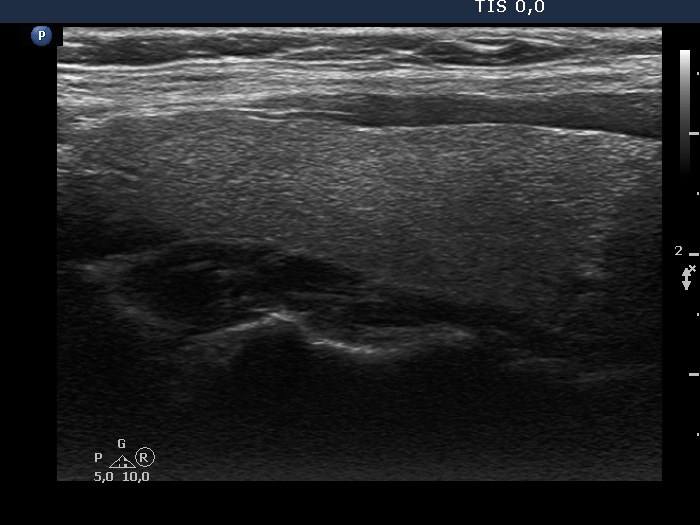

Study on 100 consecutive patients with thyroid nodule - case 041 (ultrasonographic picture 2)

Right lobe, longitudinal view.